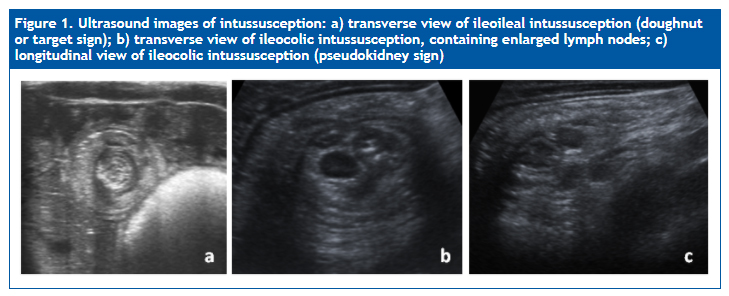

Patients typically present with intermittent abdominal pain, pulling the legs to the chest, followed by a period of lethargy. This may be accompanied by irritability, vomiting, decreased appetite and/or bloody bowel movements (currant jelly stools).2,3,5,10,13 Imaging tests play an important role in its diagnosis, which is primarily based on the clinical manifestations. Ultrasound examination, mainly, and plain chest radiography reveal characteristic findings (target, doughnut or pseudokidney signs) (Figures 1 and 2) that are very useful in the identification of this disease, as well as its localization and evaluation of potential complications.15-20

| Figure 1. Ultrasound images of intussusception: a) transverse view of ileoileal intussusception (doughnut or target sign); b) transverse view of ileocolic intussusception, containing enlarged lymph nodes; c) longitudinal view of ileocolic intussusception (pseudokidney sign) |